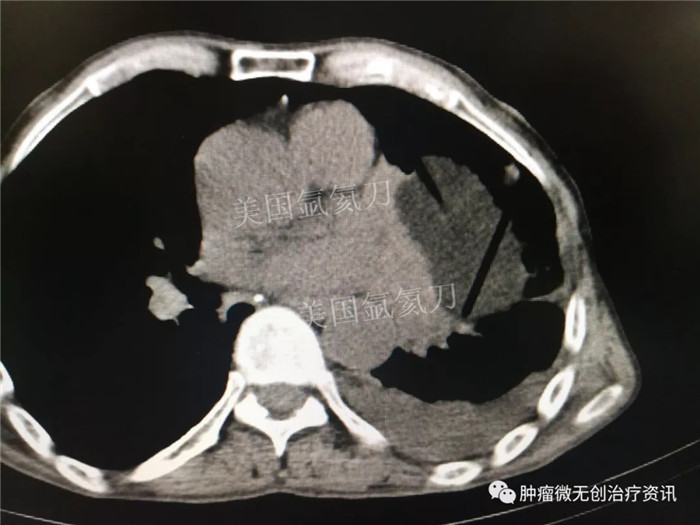

郑州大学附属郑州中心医院氩氦刀冷冻消融治疗肺部肿瘤

67岁老年男性患者,因肺部肿瘤,于7月28日行氩氦刀冷冻消融治疗。